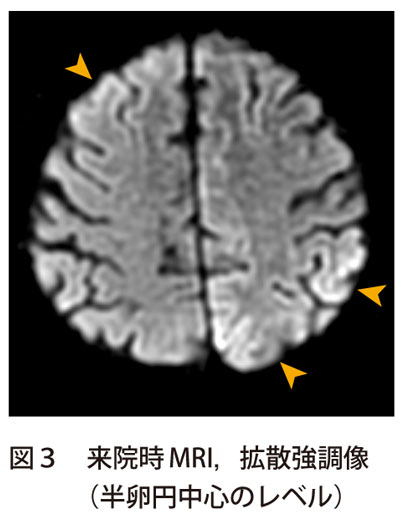

症例4 診断と解説